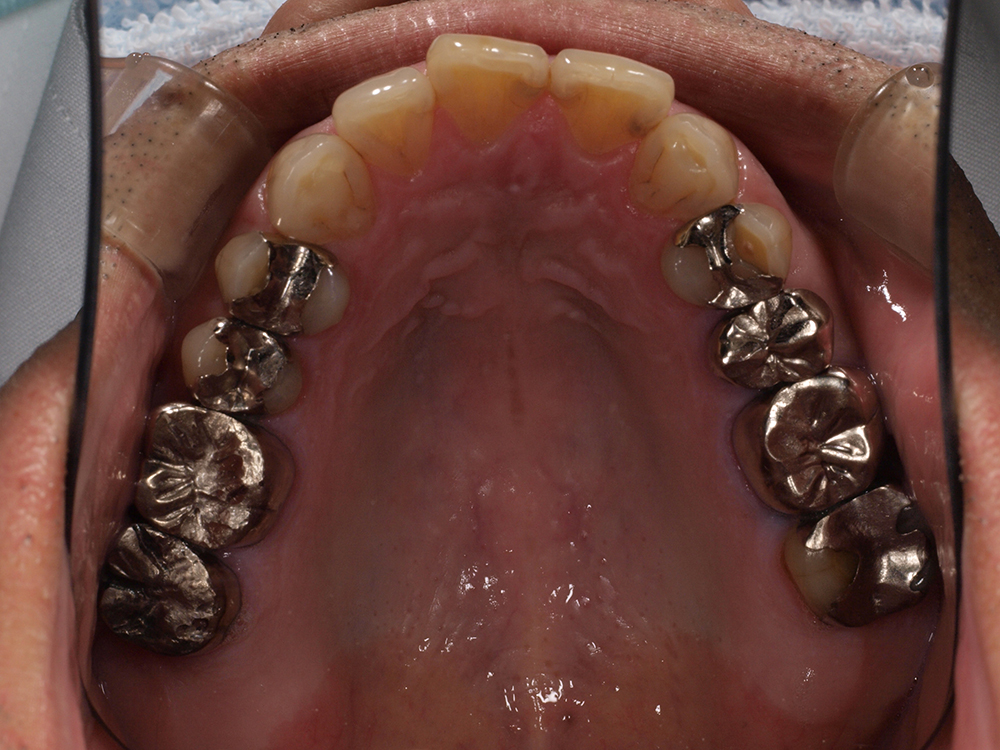

55歳 男性

- 主訴

- 前歯でしか咬めなく、食事を採るのに非常に困難で辛い

- 処置内容

- 上顎6本、下顎3本

- 治療費用

- 上顎:約230万(税込)下顎:約120万(税込)

- 治療期間

- 上顎:1年(仮歯まで8か月)下顎:8か月(仮歯まで5か月)

- リスク

- 上部構造物、仮歯の破折、術後の腫れ(3日)、人工歯根脱落リスクがあります